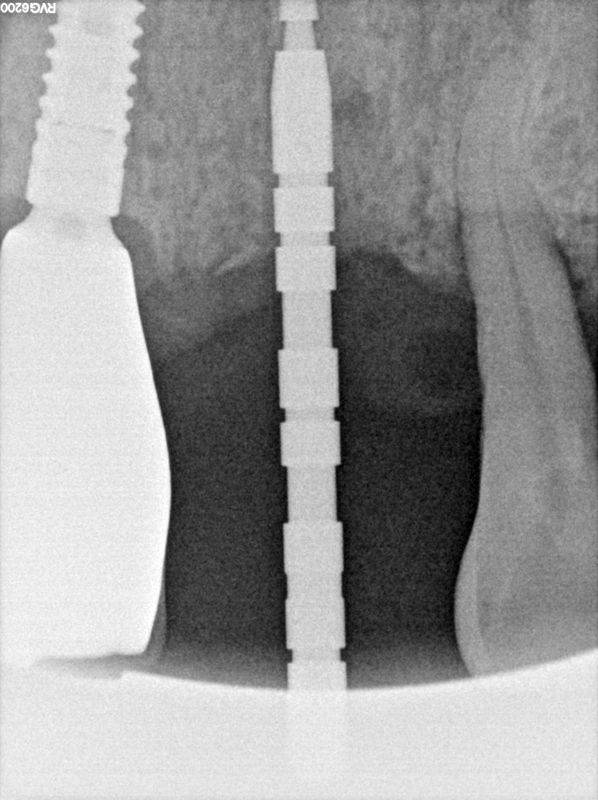

fredlibc | all galleries >> Galleries >> TZeng - 21 implant > R13.jpg

R13.jpg